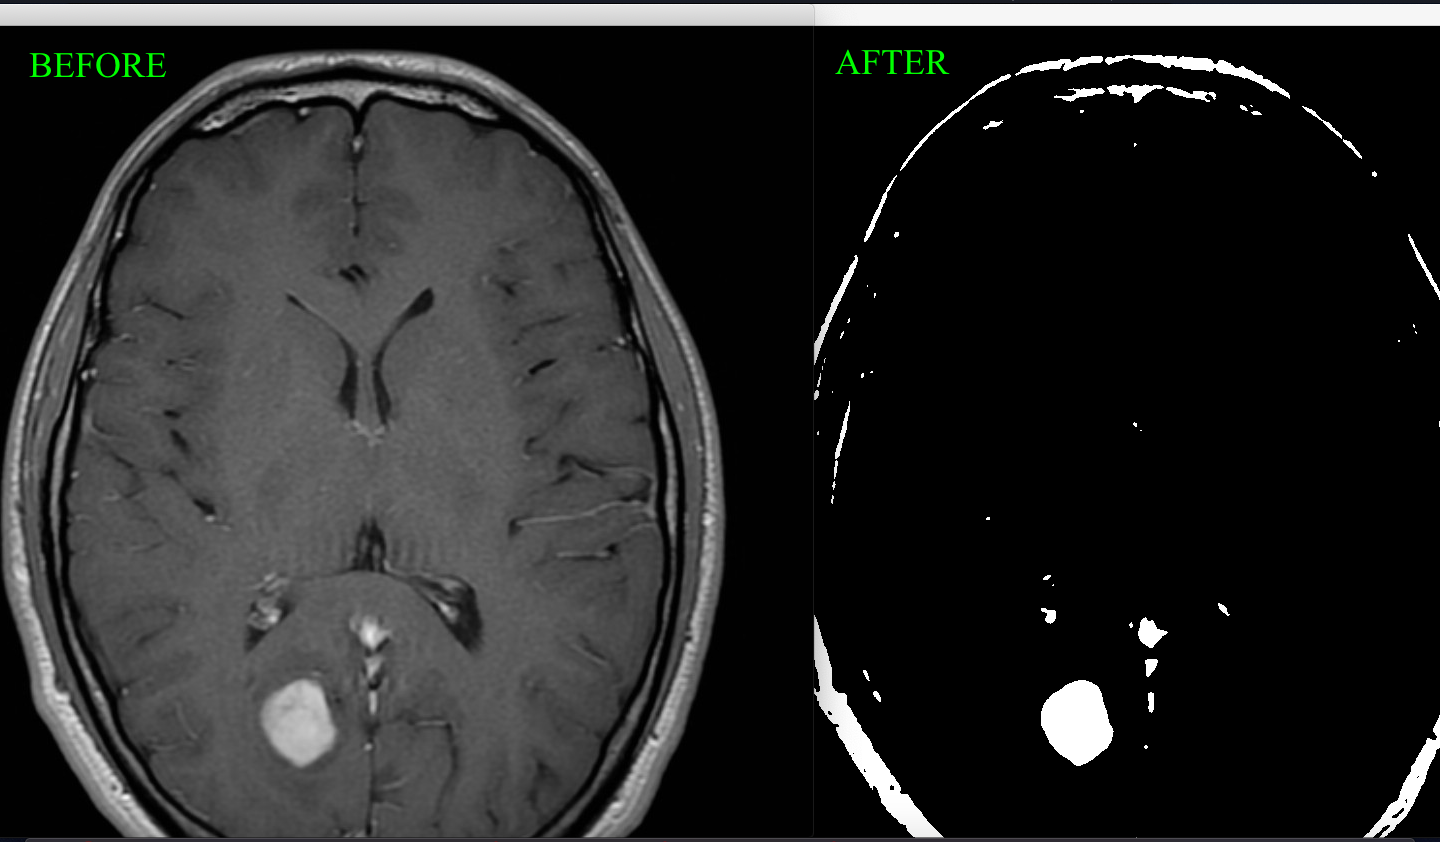

This tool takes in an image of an MRI scan, and uses various algorithms and functions to iterate through the pixels of the image and convert it to a cleaner, black and white image highlighting the specific area of the tumor. To write the code for this functionality, I had to code a grayscale filter to convert the image to grayscale, then code a median filter to reduce noise in the image, and lastly convert it to black and white. Another aspect I added was a function to determine if the tumor is a Meningioma, which means that it forms on the membranes that surround the brain. This function returns true or false depending on if the image is of a meningioma or not.

To create this tool, I had to do a lot of research. I looked at previous research papers and identified how images were manipulated to make an MRI scan clearer. I had to figure out an algorithm to identify the Meningioma. The functionality right now only checks for Meningioma on the left side of the brain. Essentially, a variable "measure" is set to 1/6 of the image's width, and since a Meningioma is attached to the membrane, the code checks for continuous white pixels within the "measure" unit to actually identify a Meningioma.